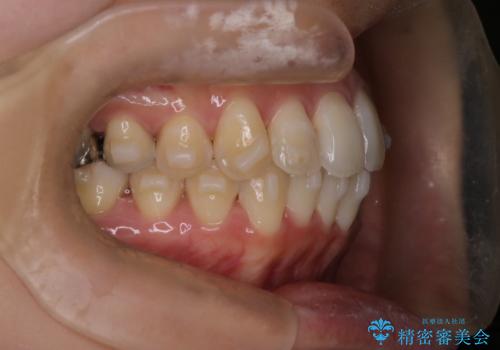

- 前歯のガタガタを主訴に来院された患者様です。

前歯の傾きも少し内側に入るように計画をたて、インビザラインにて治療を行いました。

このぐらいのガタガタであれば、インビザラインで簡単に治すことができます。